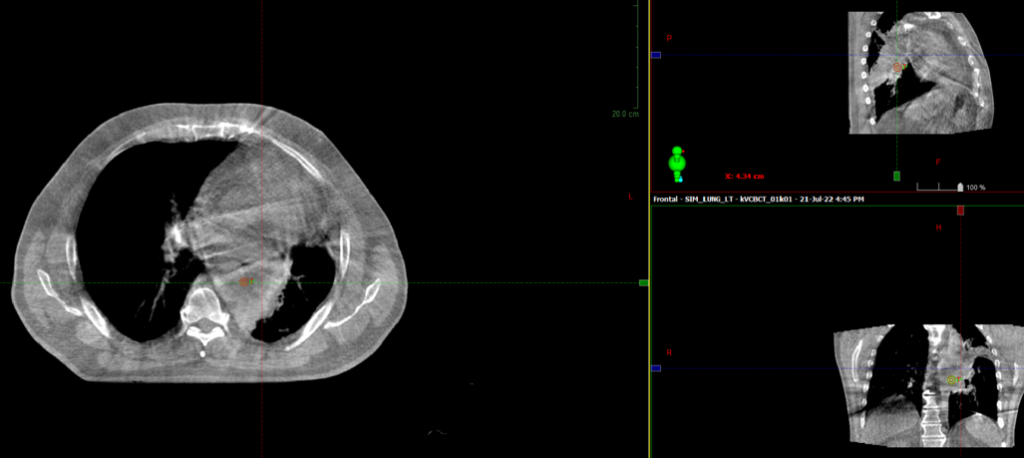

13.07.2022 выполнена КТ- топометрия органов грудной клетки с толщиной среза 2.5 мм.

21.07.2022 был запланирован первый сеанс лечения

Во время СВСТ при первом сеансе ЛТ выявлен ателектаз левого легкого

CBCT - конусно-лучевая компьютерная томография, ЛТ – лучевая терапия